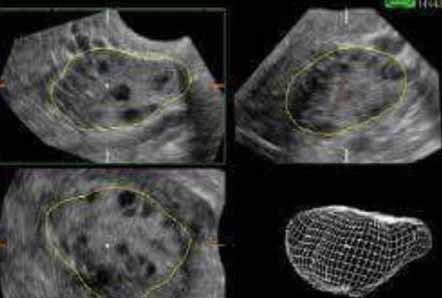

تكيس المبيض

يعتبر تكيس المبيض أكثر الحالات التي تسبب الخلل والإضطراب في الهرمونات لدى السيدات، فيوجد تكيس المبيض في حوالي 15% من السيدات اللاتي في سن الإنجاب. كما أن تكيس المبيض يشكل نسبة كبيرة من حالات تأخر الحمل، بل يعتقد أنه في حوالي 50% من الحالات التي تعاني من تأخر الحمل بسبب الزوجة يكون السبب تكيس الحمل. ولقد تم خلال الأعوام القليلة الماضية تقدم كبير في معرفة سبب تكيس المبيض وتشخيصه وعلاجه ومتابعة تقدم علاجه. وأضيف إلى مجموعة الخيارات العلاجية أخذ أقراص تعالج مضاعفاته، بل وحدث الحمل لحالات عديدة لم تستطع الطرق الأخرى علاجه، وبعد ماكان يعرف عن هذه الحالات ضعف التبويض وقلة جودة البويضات أصبح من الممكن تحسين جودة البويضات إلى الدرجة الطبيعية تماماً. لقد حدث هذا التقدم بالفعل وإرتفعت نسب الحمل في جميع الطرق الممكنة سواء كان بتنشيط التبويض أو في حالات الحقن المجهري والذي إرتفعت فيه نسب الحمل لمثل هذه الحالات إلى حدود الـ 60%. وهذه نسب أفضل من الحالات الأخرى لتأخر الحمل.

ويدعم هذا النظام أجهزة مختلفة غاية في الدقة سواء في أجهزة الموجات فوق الصوتية